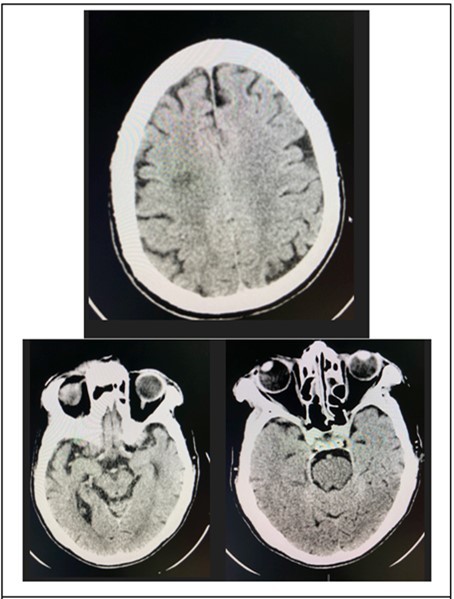

At the emergency room of the tertiary hospital, the patient had persistence of the diplopia and dizziness. The initial impression at that time was Cerebrovascular Infarct, thus a Plain Cranial CT Scan was done (conducted 6 hours after the onset of symptoms), which revealed a hypodense focus in the sub-cortical region of the right centrum semiovale extending to the right corona radiata, orbits, midbrain and pons were all normal. (Figure 2 and Figure 3)

Figure 5.Cranial CT Scan plain, axial with orbital cuts of the patient which shows un remarkable orbit, midbrain and pons findings.